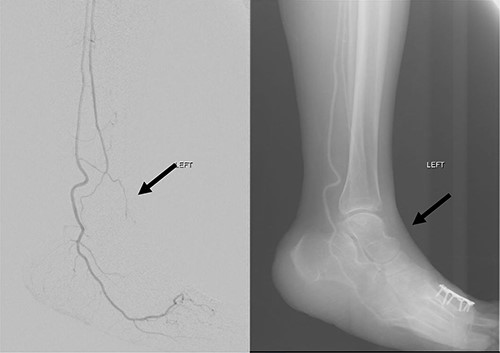

She subsequently underwent left lower limb angioplasty and stenting of the ATA with good results (Figs 4–7) and was started on antiplatelet therapy. Following successful angioplasty, she underwent early wound coverage procedure. A medially based rotation advancement flap was raised for coverage of wound defect. Patient completed 2 weeks course of broad-spectrum antibiotics post-operatively. Patient’s flap was stable and she was allowed partial weight bear over her left lower limb with Darco shoes at post-operative Day 12.

Good arterial flow of the ATA (arrow) after successful angioplasty and stenting.

Arterial flow noted at distal ATA and dorsalis pedis artery (arrow) after successful angioplasty and stenting.